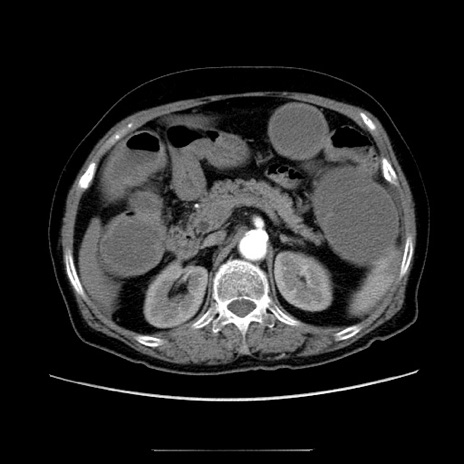

冠状断像

【症例】70歳代女性

【主訴】お腹が張る

【現病歴】1週間くらい前から腹部膨満の自覚あり。昨日夜から増悪したため、本日救急外来受診。

【身体所見】意識清明、BT 36.5℃、BP 165/106mmHg、HR 80bpm、SpO2 98%、腹部:膨満、軟、自発痛・圧痛なし、触診にて不快感あり、腸蠕動音:減弱

【データ】WBC 12600、CRP 1.04